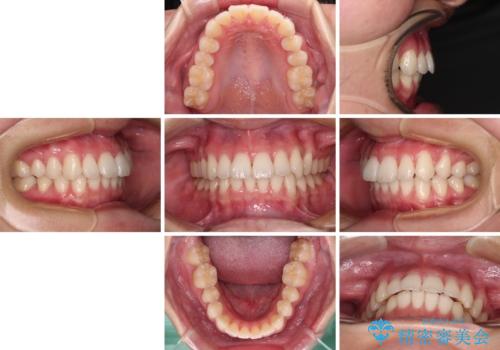

【モニター】犬歯のクロスバイトを目立たないワイヤー装置で

- 20代女性

- 矯正装置

- クリアブラケット

- 治療期間

- 1年6ヶ月

- 咬み合わせが悪いとのことで来院された患者様です。

ぱっと見はインビザラインによる矯正治療も可能と思われましたが、歯根が最も長い犬歯がクロスバイトになっており、インビザラインでは対応困難と判断され、ワイヤー装置にて矯正治療を行うこととしました。

クロスバイトになっている犬歯は、歯の移動に伴い装置を張り替えていくことで対応することとしました。